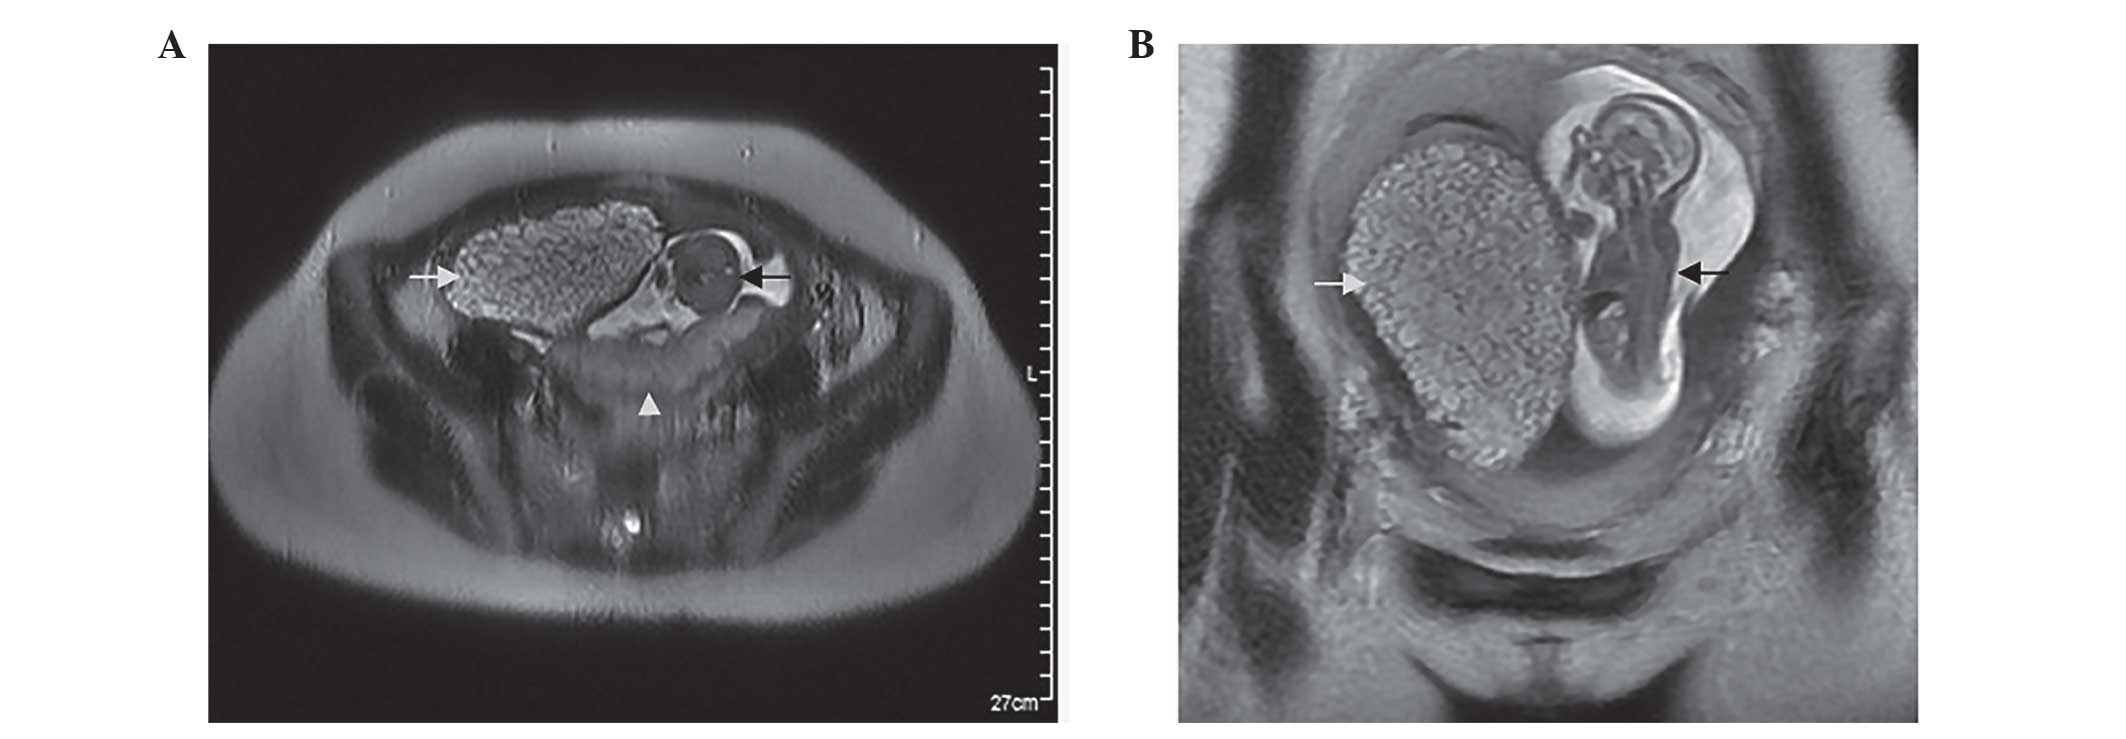

Hydatidiform Mole Mri

Complete hydatidiform mole | Radiology Reference Article | Radiopaedia.org Invasive mole | Radiology Reference Article | Radiopaedia.org Molar pregnancy | Radiology Reference Article | Radiopaedia.org Molar pregnancy | Radiology Reference Article | Radiopaedia.org | Hydatidiform Mole Mri